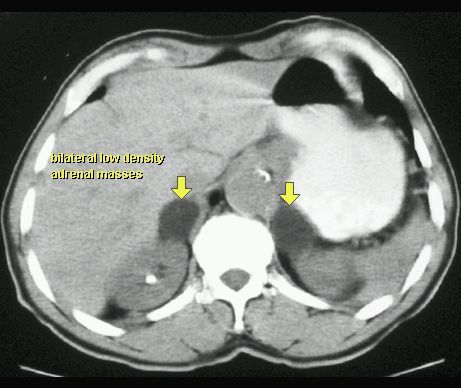

TK

GRUCZOLAK NADNERCZA